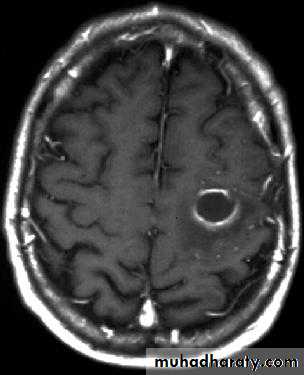

• B. Radiological Investigations:• CT or MRI is the investigation of choice.

• CT Brain is performed with and without contrast.

• MRI is done with gadolinium enhancement.

• They will show a single (or multiple) space occupying lesion that is well delineated with an enhancing wall, with variable surrounding oedema.

Brain Abscess MRI